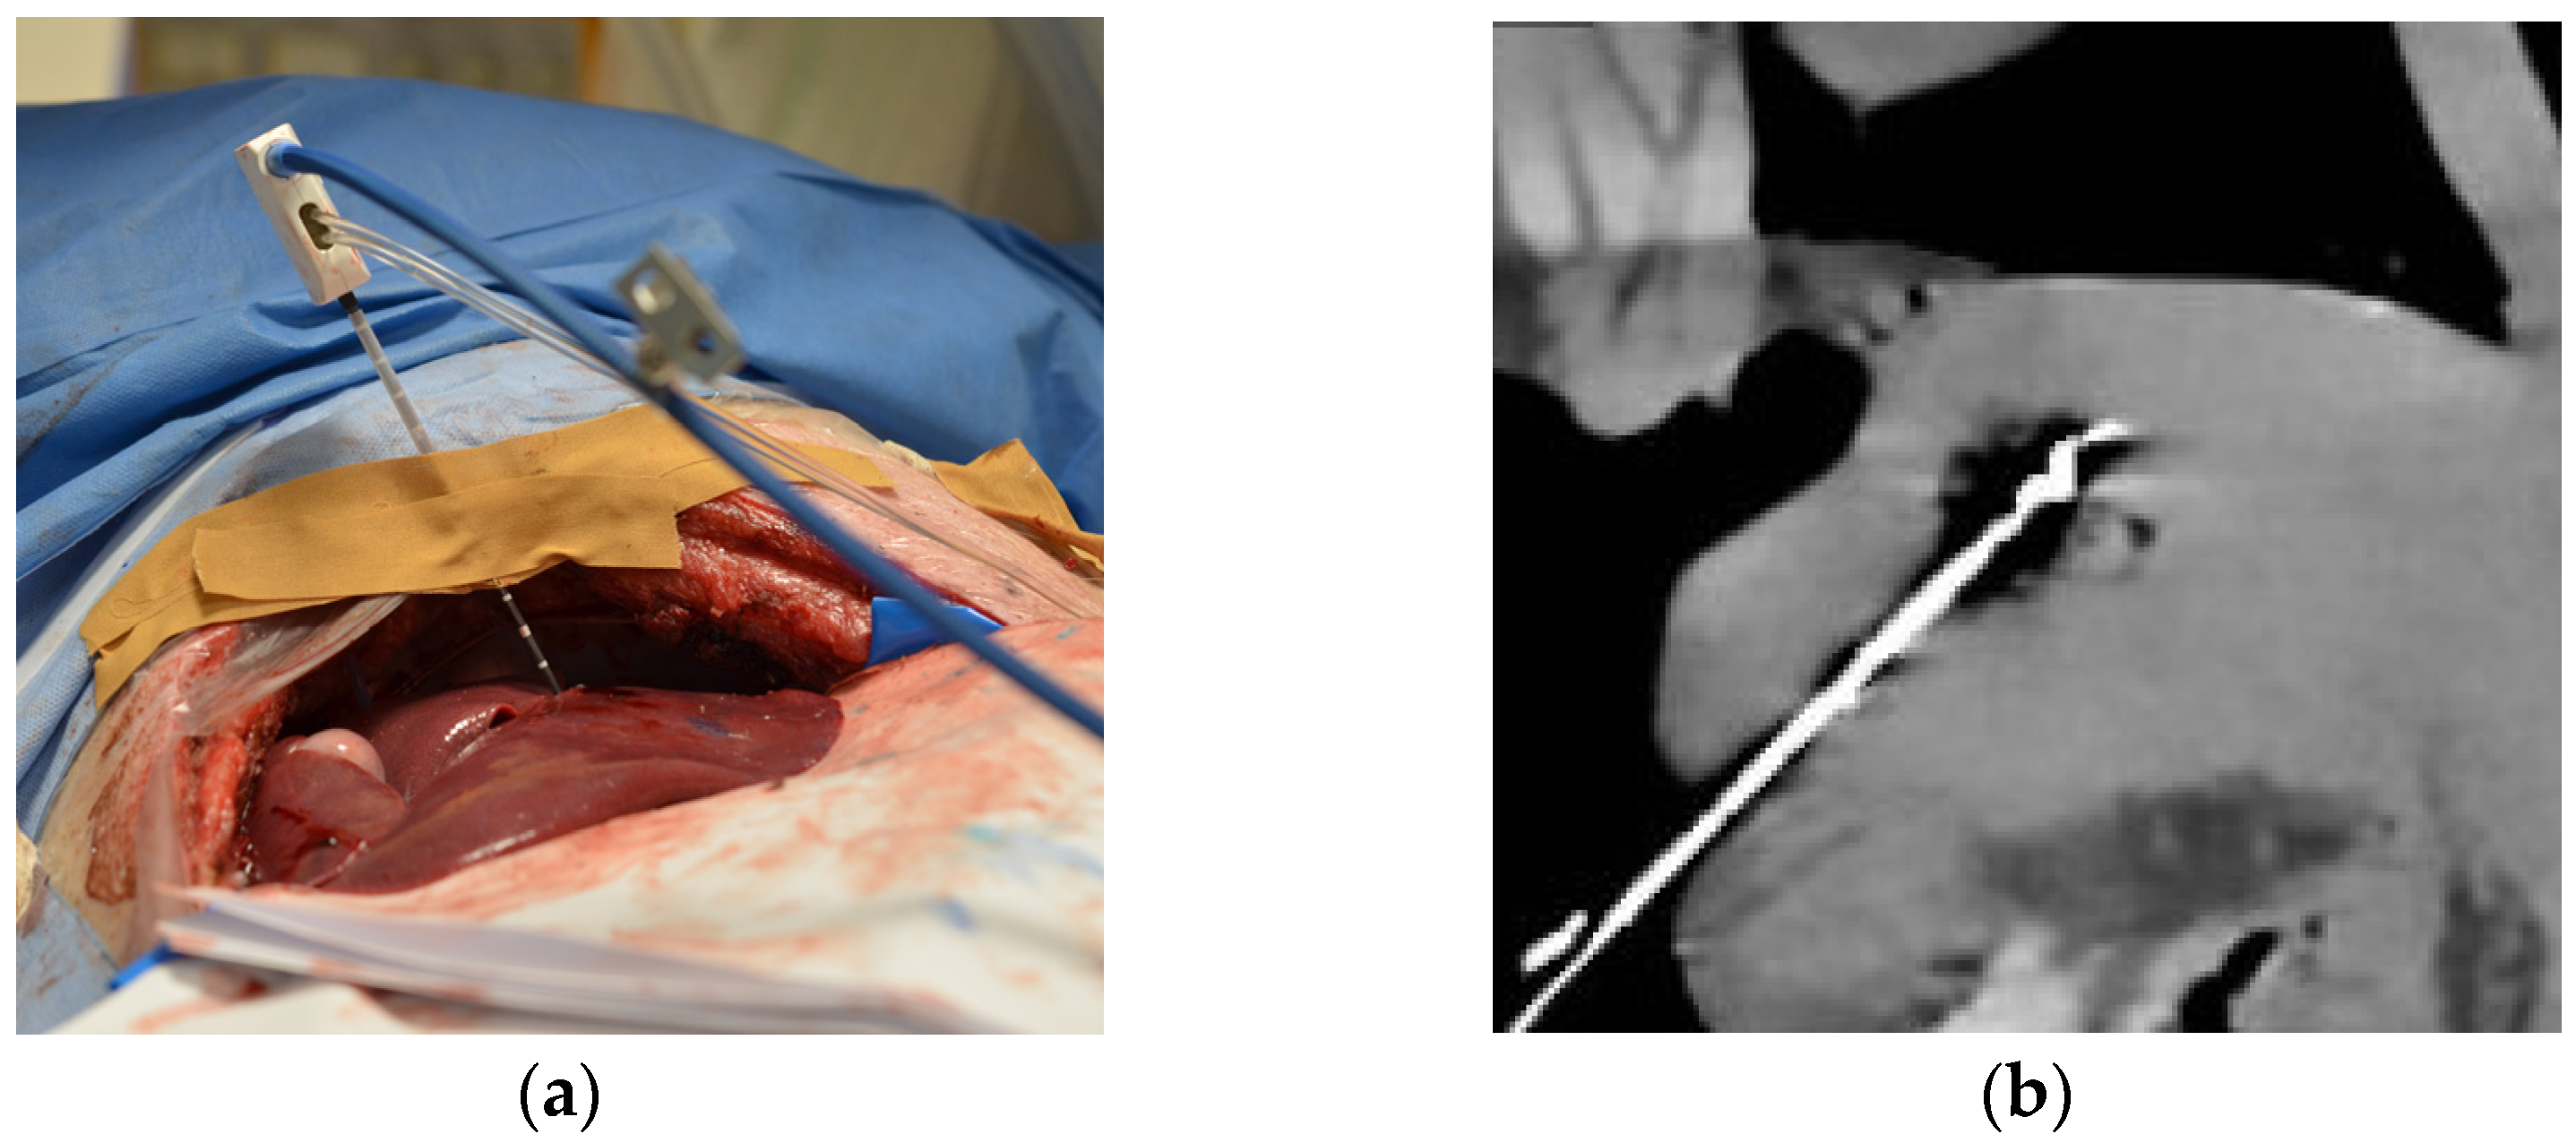

Four MWAs were performed on normal liver tissue in a ventilated 6-month-old female domestic pig under general anesthesia. The animal was housed in the central animal husbandry of the Charité with compliance to 2010/63/EU-directives and recommendation of the GM-Solas (Society for Laboratory Animal Science, Freiburg, Germany) for pig husbandry. The experiments were conducted in 2020 using the latest CT technology as a proof of concept for further clinical trials. The porcine liver is similar to human liver parenchyma, and the artifacts due to respiration and heart action serve as a realistic model. The liver was exposed in a sterile environment to ensure better access to the organ with the ablation and temperature probes (Figure 1a). For each of the three ablations successfully performed, the MWA probe (AveCure, MedWaves Incorporated, San Diego, CA, USA) power was set to 100 W. One CTT dataset of the liver was acquired without thermoablation. The probe was placed in porcine liver for the respective ablation in such a way that there was sufficient distance to the other ablation areas. During each MWA, 20 spectral acquisitions were acquired without table movement using 16 cm detector coverage (Canon Aquilion ONE Prism; Canon Medical Systems, Otawara, Japan). Scan parameters: rapid kVp switching between 80 and 135 kVp, 1 s rotation time, 500 mA tube current. The first scan was acquired right at the beginning of the ablation, and each further scan at 30 s intervals throughout the 5 min of ablation. Maximum temperature was reached when the 10th scan was acquired (Tmax), and the probe cooled down during the remaining session (Figure 1b). Another 10 CT scans after the energy gift of the MWA were acquired every 60 s, covering the postablation phase. The animal was euthanized at the end of the experiment, and the liver was removed for histopathological assessment.

Figure 1.

Experimental setup of computed tomography (CT)-based thermography (CCT): (a) Intraoperative photograph showing the animal under general anesthesia with the liver exposed and the microwave ablation (MWA) probe inserted; (b) CT image showing inserted MWA probe in the liver at the end of heating phase reaching maximum temperature (Tmax) before cooling down. In the same axis with a clear representation of the ablation probe and zone, the images for the rating were set.